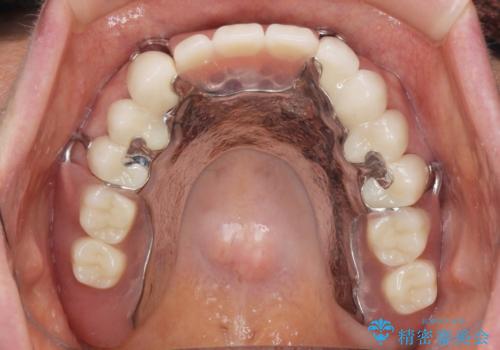

前歯のねじれをマウスピース矯正インビザラインで治療